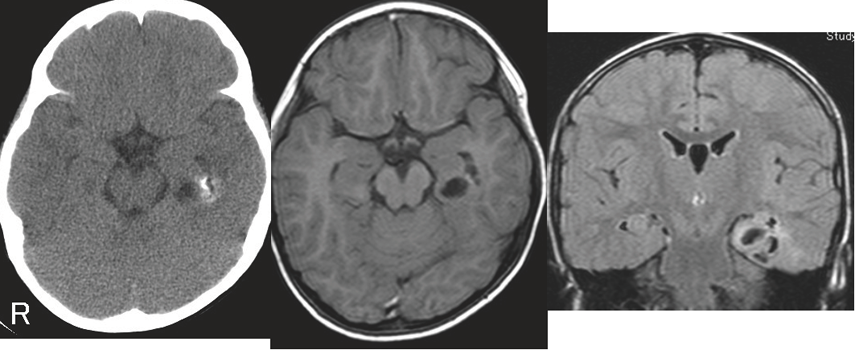

構造的病因:左内側側頭葉神経節膠腫(ganglioglioma)による焦点てんかん:7歳男児のCT、MRI

CT上内側側頭葉に石灰化、MRI上嚢胞性病変を認める。3歳発症の焦点意識減損発作(動作停止、眼球偏位、意識混濁を伴う焦点発作)が数十秒持続。ときに両側に波及し、焦点起始両側強直間代発作となる。発作は多剤に抵抗性であったため、病変部切除術が行われた。